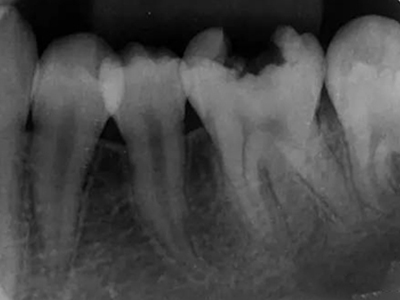

年轻恒牙龋指的是儿童萌出不久的第一恒磨牙龋病和上颌恒切牙龋病,其中第一恒磨牙龋病占年轻恒牙龋的90%,发病早,进展快,可表现为白垩色斑片、点隙窝沟墨浸状龋坏或龋洞。本病的发生和年轻恒牙的特点以及儿童饮食、口腔卫生等因素有关。

年轻恒牙龋好发于第一、二恒磨牙(牙合)面、邻面,上颌中切牙邻面,多为急性龋,龋坏进展快。平滑面的早期龋多为白垩色的斑片,点隙窝沟的早期龋多为浸墨状,表面粗糙。如果早期龋不及时治疗,可逐渐形成大而深的龋洞,易导致牙髓炎和根尖周炎。

年轻恒牙龋一般可进行充填治疗,对于早期的年轻恒磨牙,提倡采用微创的预防性树脂充填术、改良的预防性树脂充填术;深龋必要时考虑二次去腐修复。日常注意饮食,重视口腔卫生,考虑局部使用氟化物防龋,如含氟牙膏、含氟漱口水等,进行预防。对于年轻恒磨牙,可早期进行窝沟封闭,定期进行口腔检查。